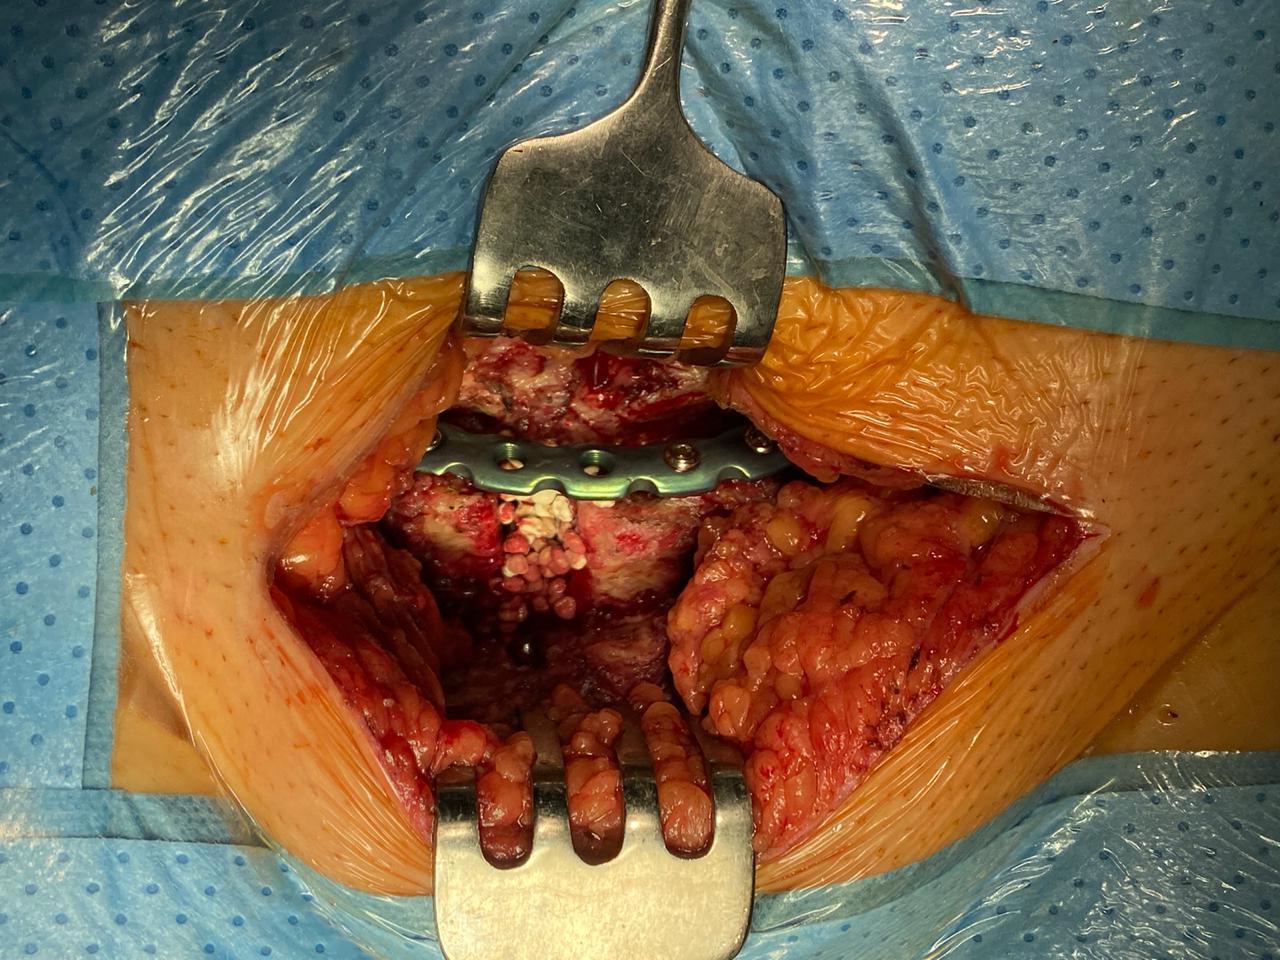

После обследования и подготовки пациентки была выполнена операция: «Резекция лобкового симфиза. Металлодез переднего полукольца таза пластиной. Пластика остеопласитческим материалом на основе гидроксиапатита». Оперативное вмешательство заключалось в резекции лобкового симфиза до здоровых тканей. Произведено удаление фрагмента кости 2×2 см. Далее выполнены металлодез переднего полукольца таза пластиной, пластика остеопластическим биокомпозиционным материалом на основе гидроксиапатита (остеопласитческий материал на основе гидроксиапатита; рис. 3). Осуществлена установка дренажа.

Рис. 3. Пластика дефекта лобкового симфиза остеопластическим биокомпозиционным материалом на основе гидроксиапатита у пациентки Д.

Fig. 3. Plastic surgery of the defect of the pubic symphysis.